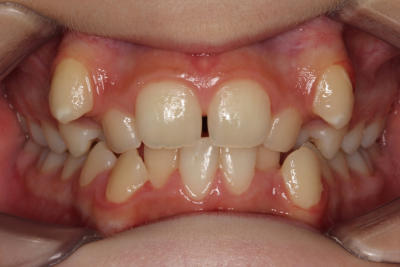

Crowding with lateral open bite – Child case